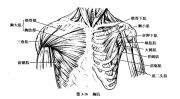

| 2021年7月26日 (一) 20:03 | 胸大肌.jpg (文件) |  |

100 KB | Uploaded with SimpleBatchUpload | 3 |